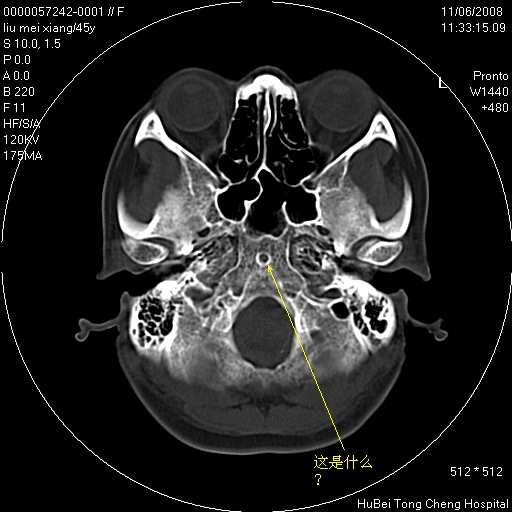

以下是引用guanaishengming在2008-11-6 12:02:00的发言:[br]正常变异,没有临床意义